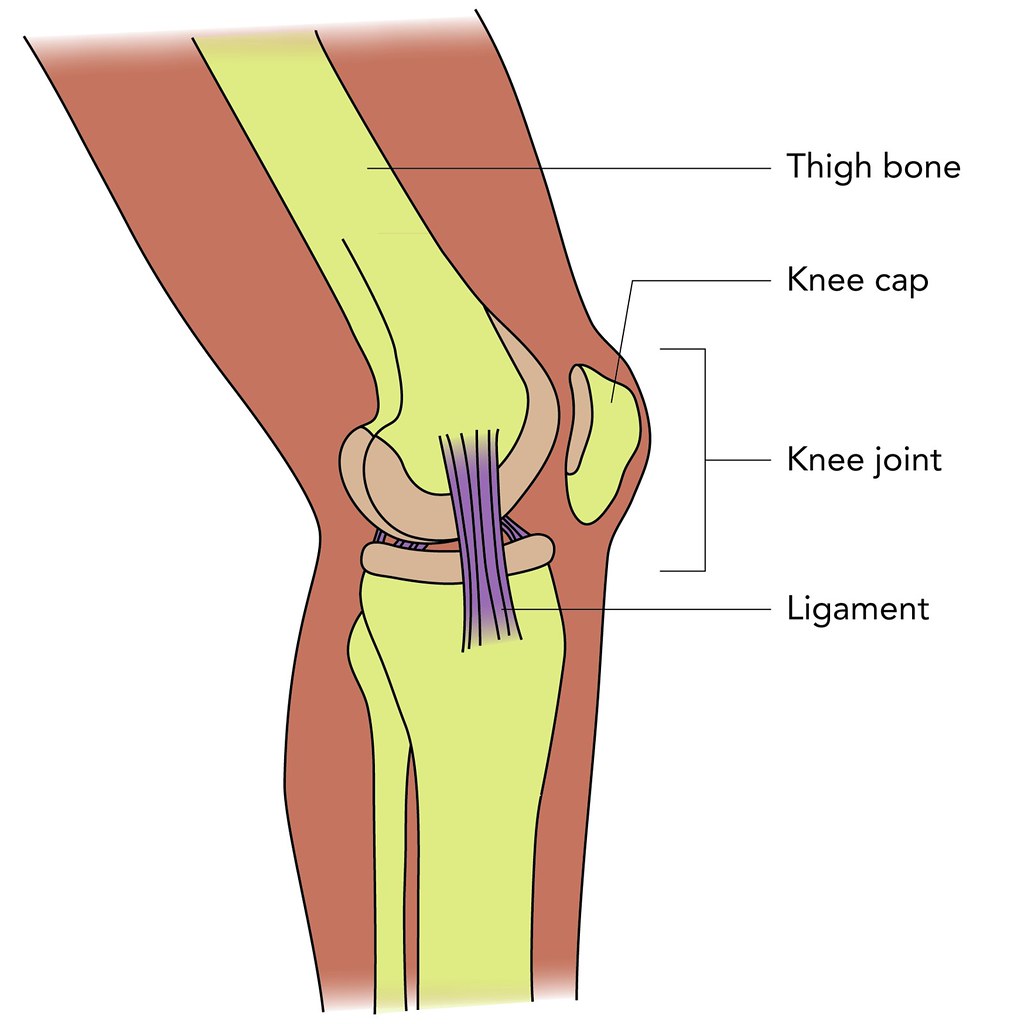

관절에 맞는 주사 중 가장 흔한 것은 뼈주사와 연골주사인데 이 둘을 같다고 생각하는 경우가 많다.

일명 뼈주사라고 불리는 관절주사는 스테로이드 성분으로 우윳빛을 띤다.

강력한 소염작용을 해 염증과 통증을 개선하는 효과가 있으며 효과가 빠르다.

초기 및 중기 관절염에 주로 사용하며 통증이 심하거나 부종이 심할 때 효과가 좋다.